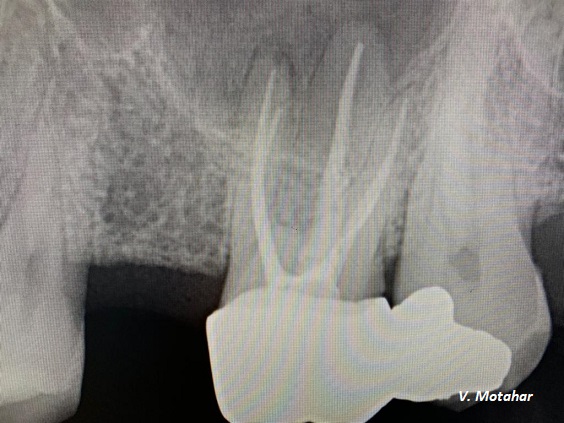

Root Canal treatment on Lower molar tooth immediate after the Root Filling!

before

after

Root canal treatment on three rooted tooth! which had 4 canals!